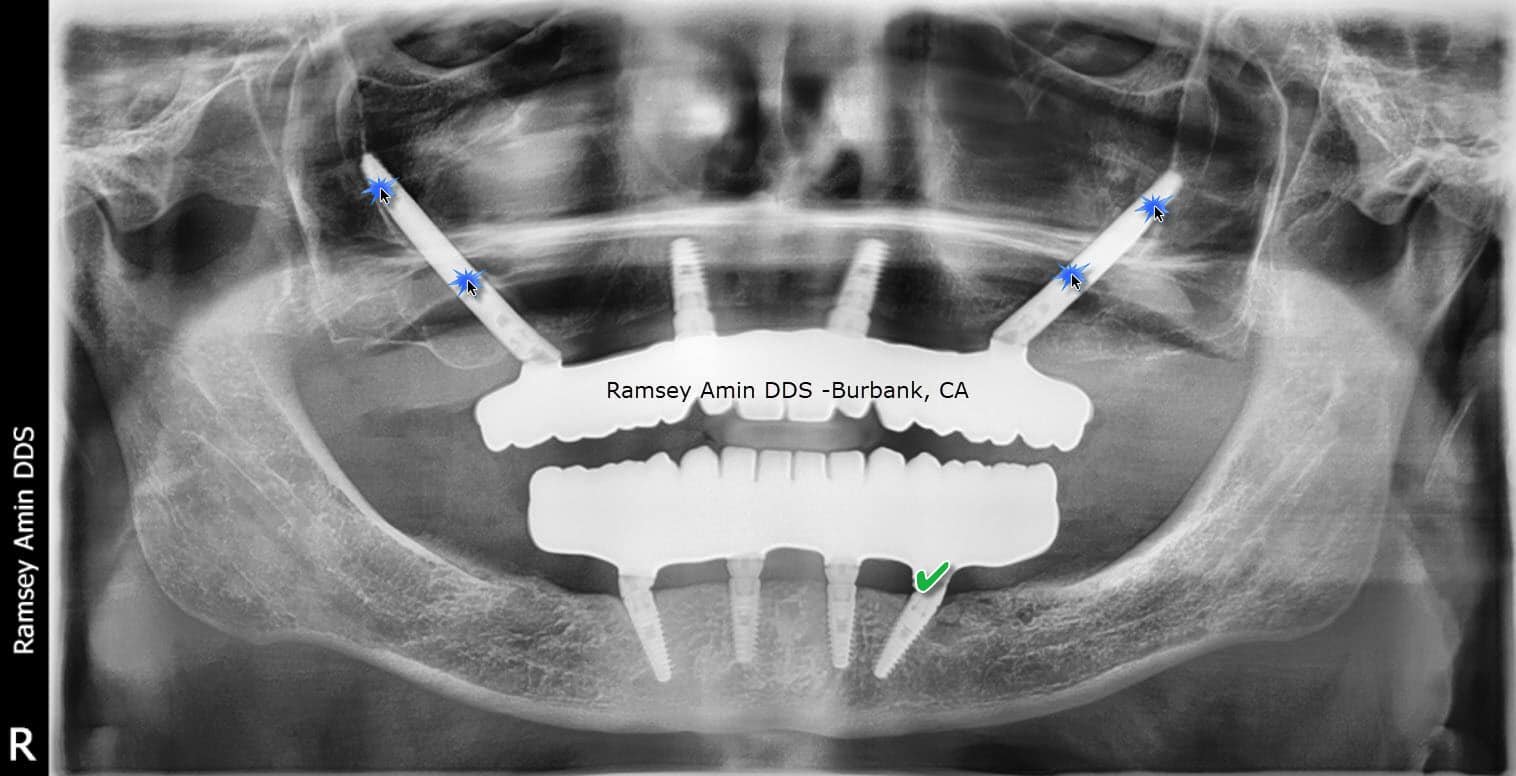

From burbankdentalimplants.com

AllOn4 Dental Implant Problems And Complications Dental Implant Problems Years Later There are two primary types of dental implant failures. In this case, call your dentist or seek care. The james clinic offers orthodontic treatment and emergency dentistry in ireland. Causes of dental implant failure. Learn about the causes and signs of dental implant failure and how to deal with it. Absolute implant survival was 94.74%; What are the complications of. Dental Implant Problems Years Later.